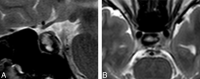

Background and purpose: Cystic pituitary adenomas may mimic Rathke cleft cysts when there is no solid enhancing component found on MR imaging, and preoperative differentiation may enable a more appropriate selection of treatment strategies. We investigated the diagnostic potential of MR imaging features to differentiate cystic pituitary adenomas from Rathke cleft cysts and to develop a diagnostic model.

Materials and methods: This retrospective study included 54 patients with a cystic pituitary adenoma (40 women; mean age, 37.7 years) and 28 with a Rathke cleft cyst (18 women; mean age, 31.5 years) who underwent MR imaging followed by surgery. The following imaging features were assessed: the presence or absence of a fluid-fluid level, a hypointense rim on T2-weighted images, septation, an off-midline location, the presence or absence of an intracystic nodule, size change, and signal change. On the basis of the results of logistic regression analysis, a diagnostic tree model was developed to differentiate between cystic pituitary adenomas and Rathke cleft cysts. External validation was performed for an additional 16 patients with a cystic pituitary adenoma and 8 patients with a Rathke cleft cyst.

Results: The presence of a fluid-fluid level, a hypointense rim on T2-weighted images, septation, and an off-midline location were more common with pituitary adenomas, whereas the presence of an intracystic nodule was more common with Rathke cleft cysts. Multiple logistic regression analysis showed that cystic pituitary adenomas and Rathke cleft cysts can be distinguished on the basis of the presence of a fluid-fluid level, septation, an off-midline location, and the presence of an intracystic nodule (P = .006, .032, .001, and .023, respectively). Among 24 patients in the external validation population, 22 were classified correctly on the basis of the diagnostic tree model used in this study.